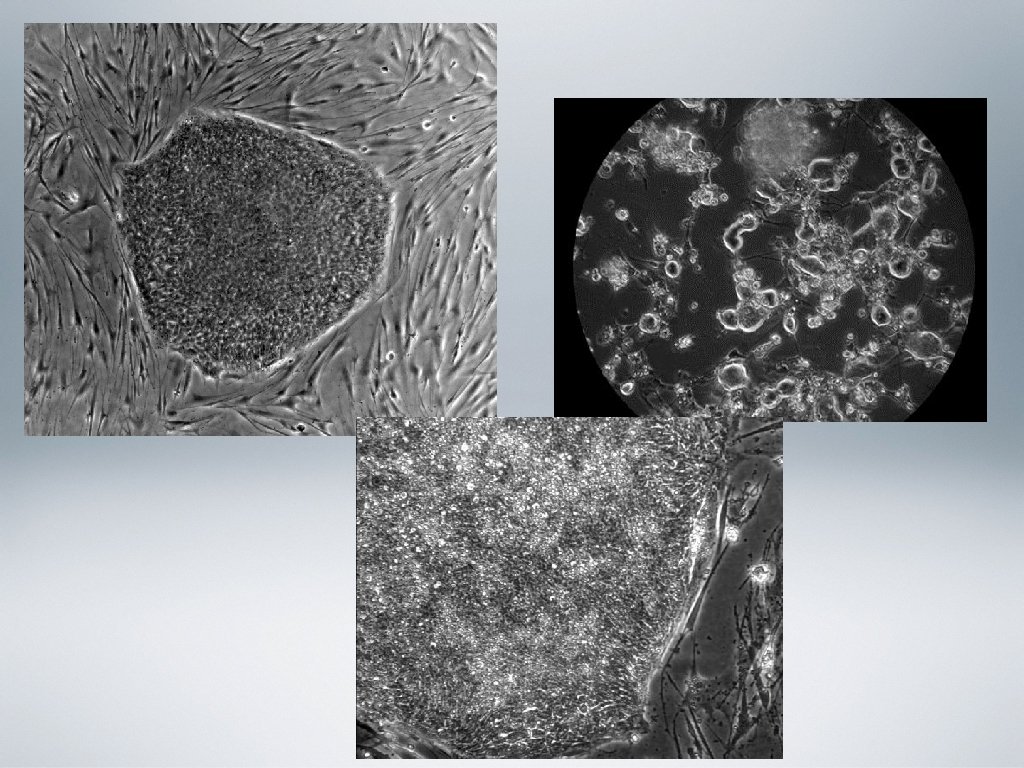

Zer dira? • Zelula-amak organismo zelulanitz guztietan agertzen diren zelulak dira, guztiz ezberdindu edo espezializatuak. Mitosian bidez zatitzeko gaitasuna dute eta zelula espezifiko edo zelula ama berriak birsortzen dituzte. • Beste zelula mota batzuk sortzeko gaitasuna dute, zelula mota horiekin giza gorputzeko ehunak eratuz.

• Zelula-amak asimetrikoki zatitzeko gaitasuna dute, bi zelula -umeren sorrera ahalbidetuz. • Batek ama zelularen ezaugarri berdinak (autoberritzea) • Besteak ingurumeneko baldintza egokiak izanez gero bereiztu egingo da. • Organismo heldu baten ehun guztiek izaten dute ama zelula kopuru bat , hauen berritze periodikoa ahalbidetzen dutenak edo behar denean birsortzea.

• Ama-zelula enbrionarioak: • Embrioiaren blastozisto (desberdintze prozesurik hasi ez duten enbrioi goiztiarra) fasearen barneko masa zelularra da. • Pluripotenteak. • Minbizia, diabetesa, bizkarrezur muineko lesioak, esklerosi anizkoitza eta beste hainbat gaitz sendatu eta artatzeko erabilgarriak. • Enbrioietatik hartzen dira; zehatzago blastozitoetatik.